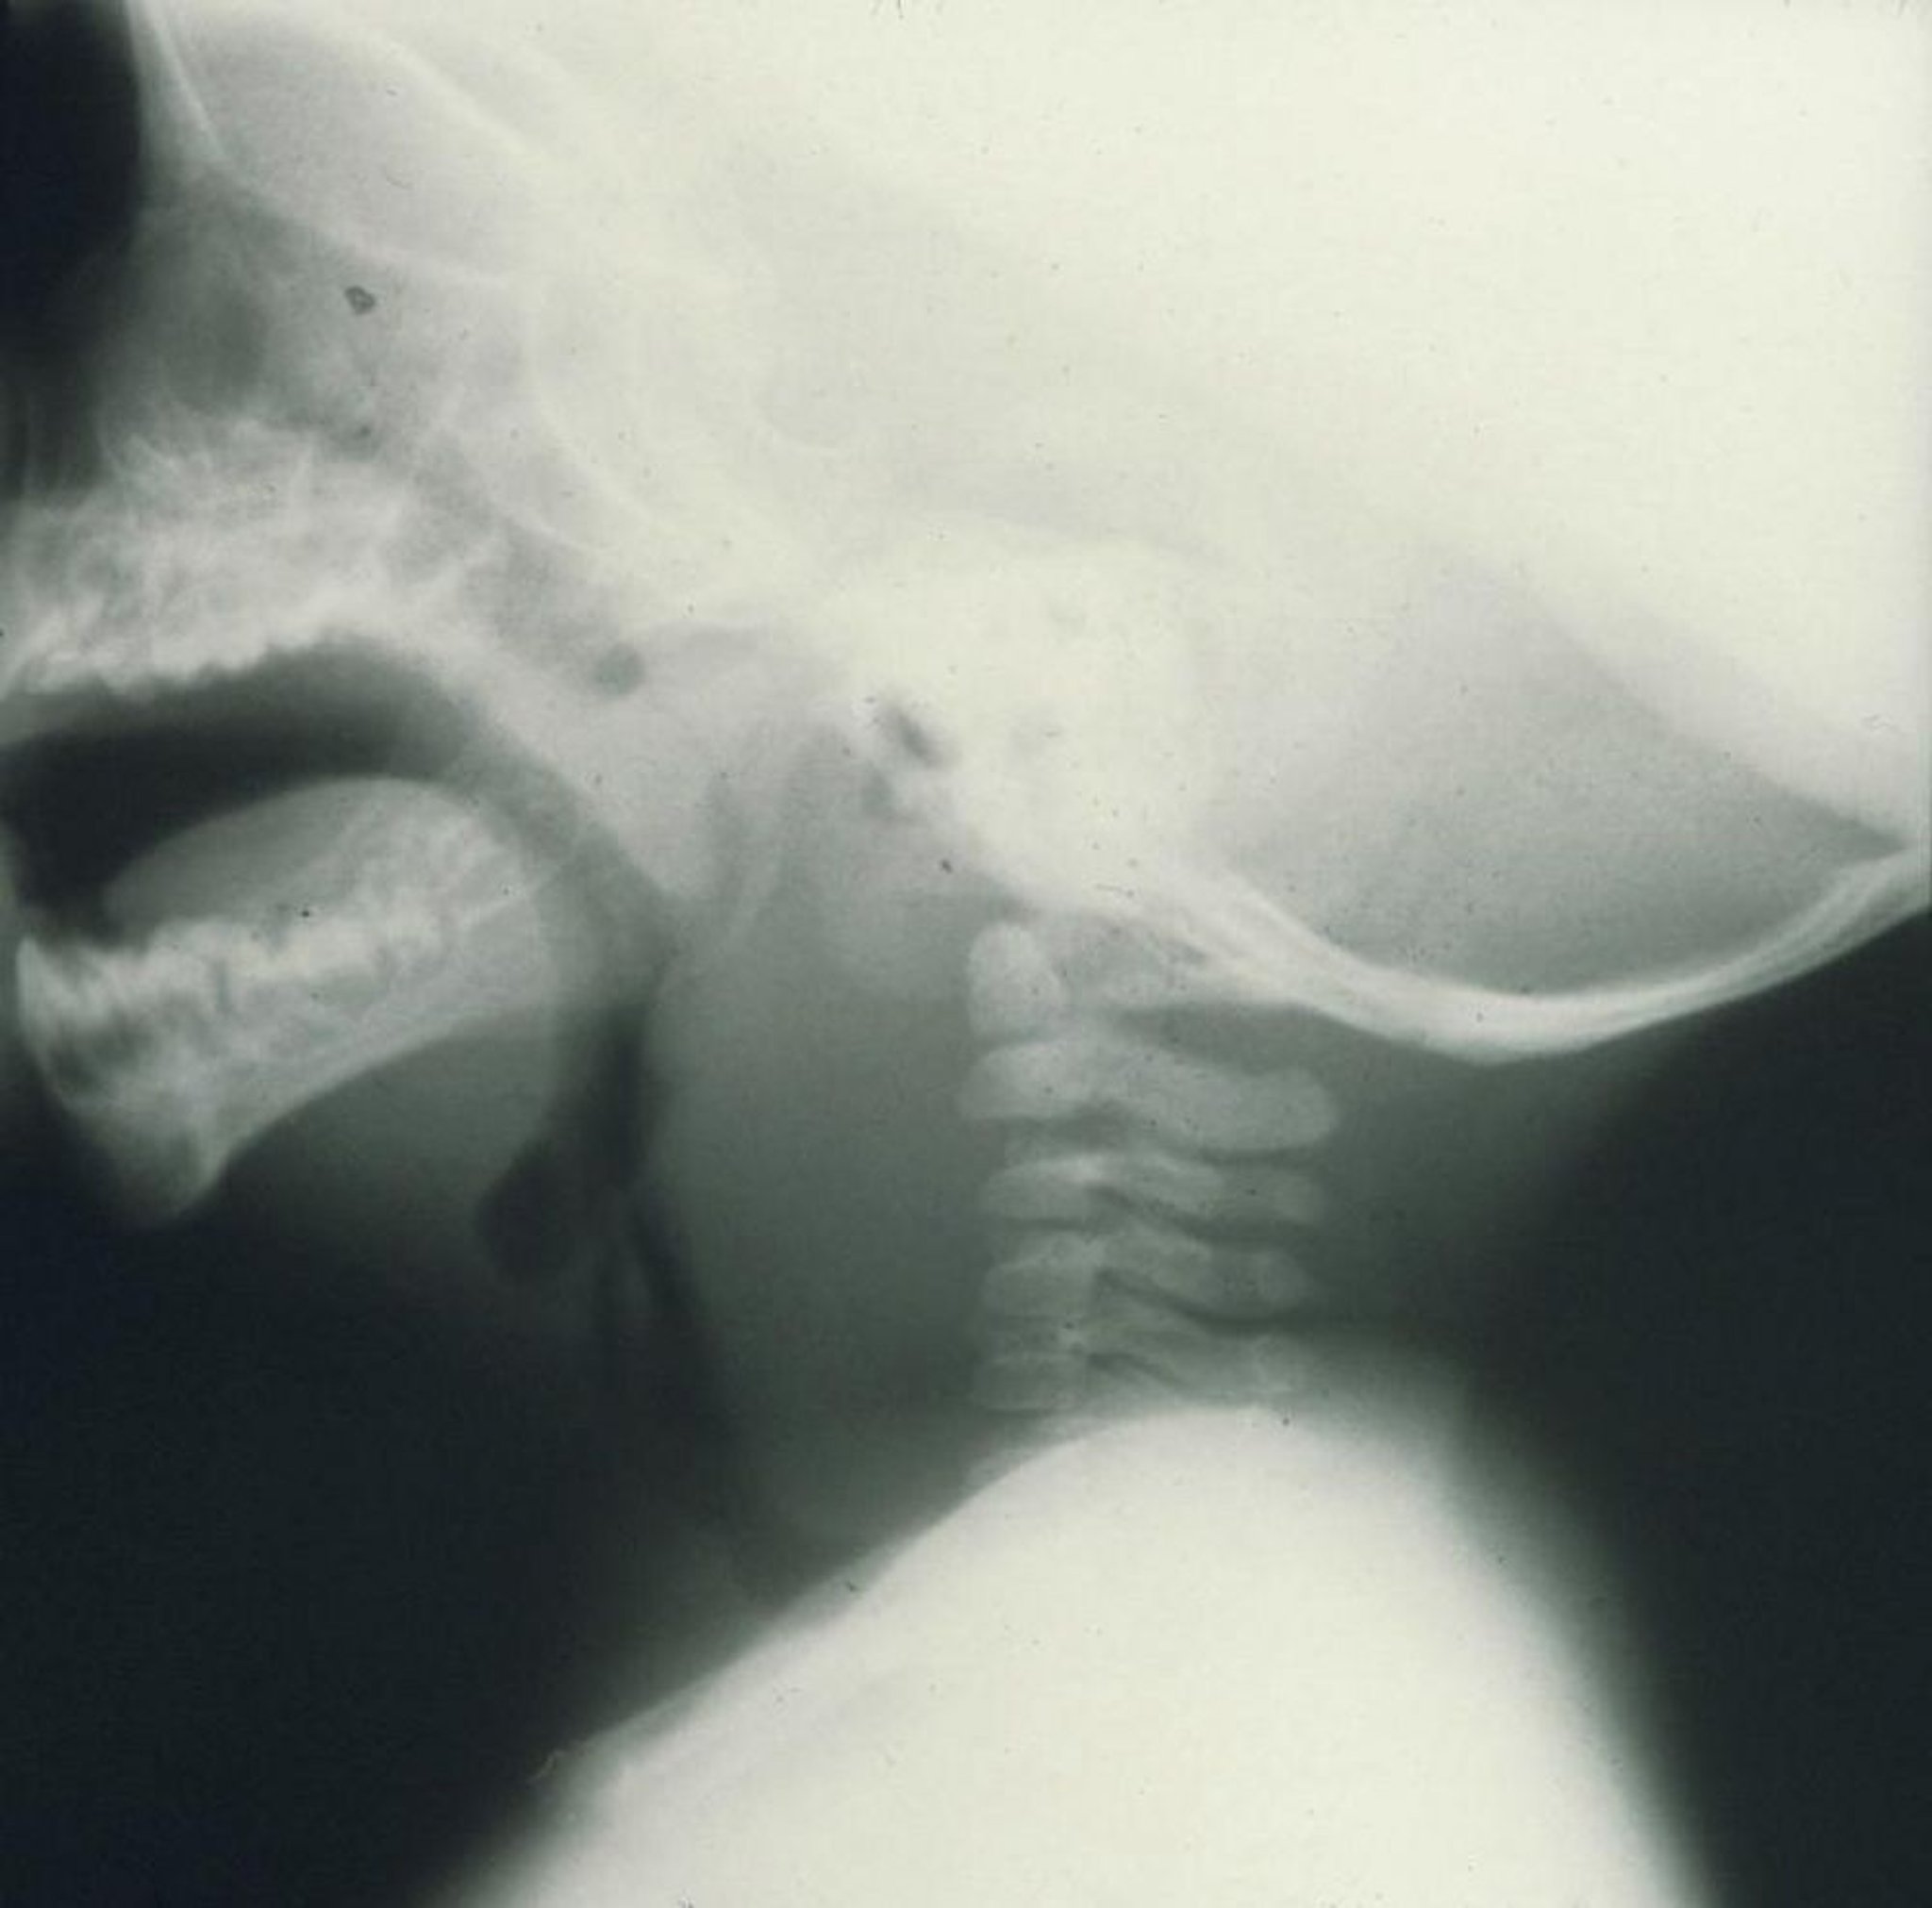

Заглоточный абсцесс

Боковая рентгенограмма выраженного отека в передней части шейного отдела позвоночника, вызванного заглоточным абсцессом у ребенка.

Image provided by Clarence T. Sasaki, MD.